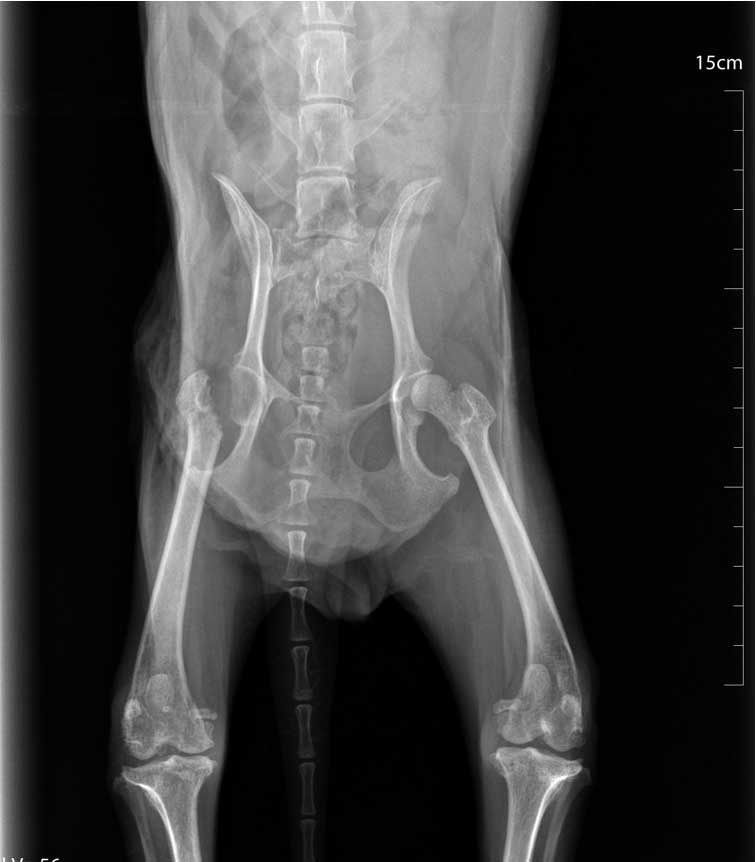

Femoral Head and Neck Ostectomy (FHO) je kirurški zahvat kojim se uklanja glava i vrata bedrene kosti. Najčešće se koristi kod teških promjena kuka, luksacija ili bolnih degenerativnih bolesti.

Cilj operacije je uklanjanje izvora boli u zglobu kuka.

Nakon zahvata stvara se tzv. „lažni zglob” od mišića i vezivnog tkiva. Iako zvuči drastično, većina pasa se vrlo dobro prilagodi novom stanju.

Zahvat se češće preporučuje manjim i srednje velikim psima. Prednost FHO-a je to što ne zahtijeva ugradnju implantata.